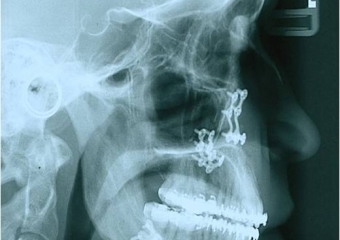

Telerradiografia após a cirurgia